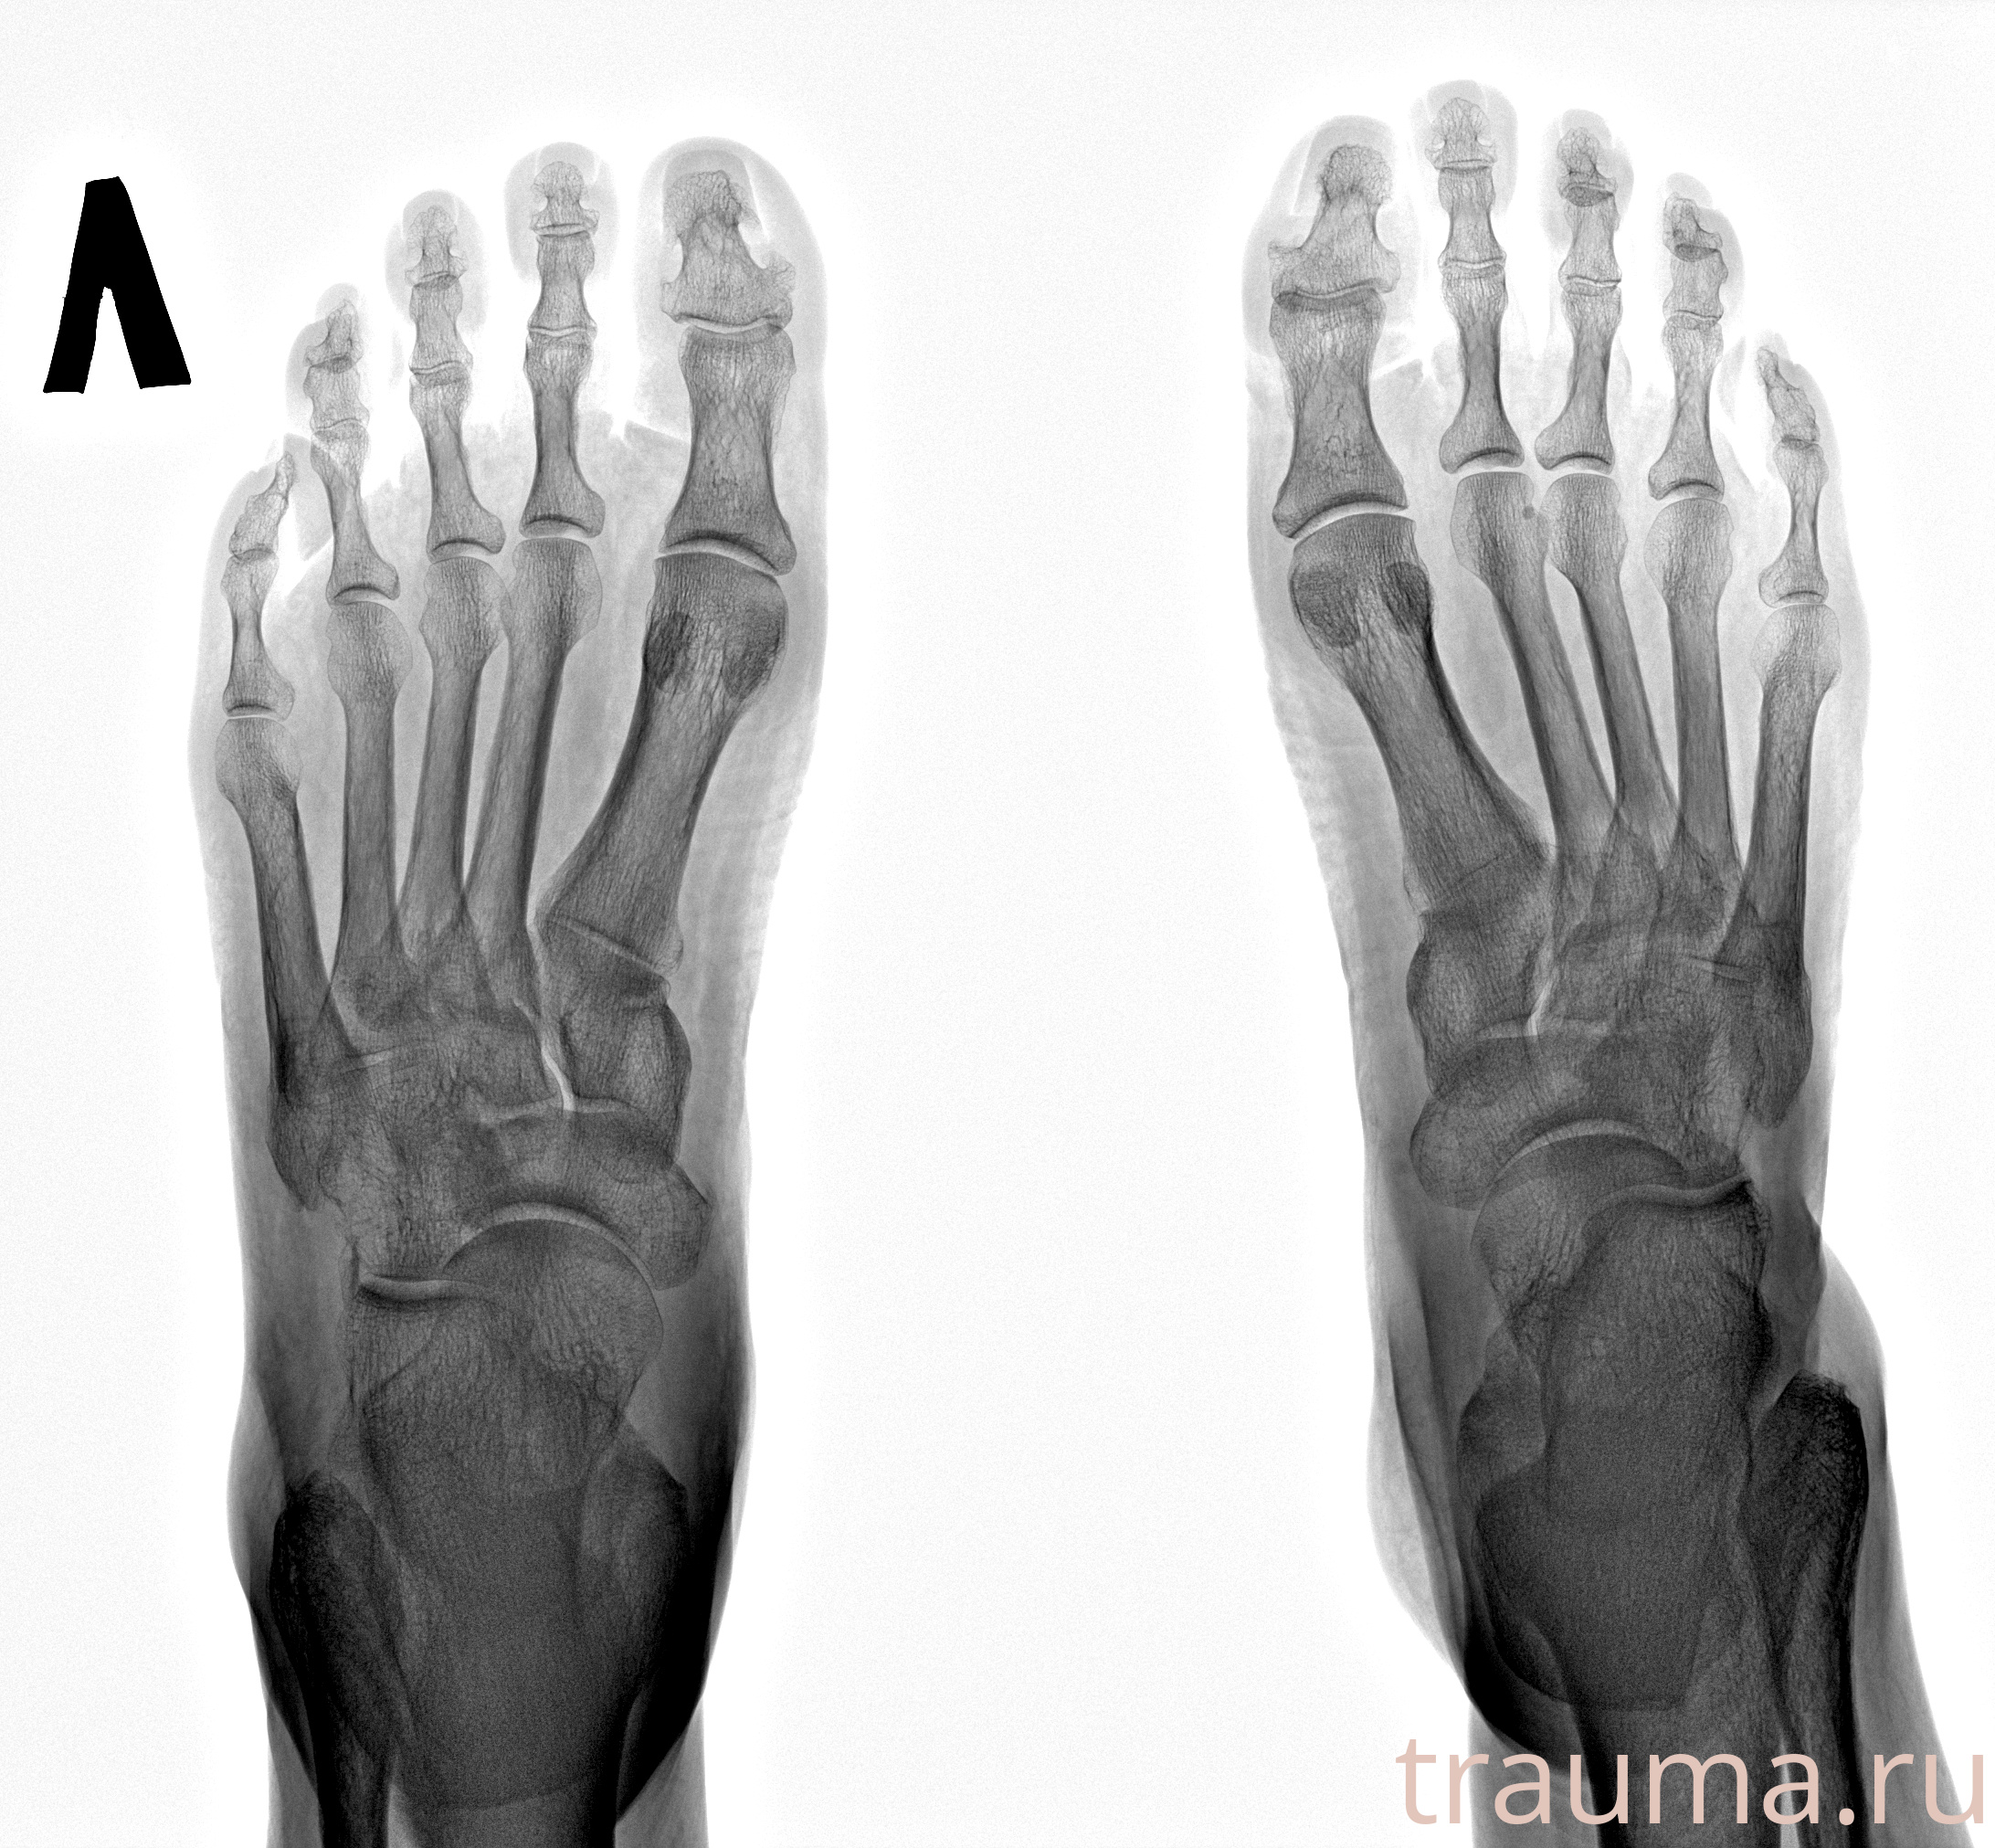

Рентгенограммы

Рентген на дому: по вашему адресу приезжает врач-рентгенолог, травматолог-ортопед с мобильным рентгеновским аппаратом, проводит диагностику травмы или заболевания, делает необходимые рентгенограммы, дает рекомендации по дальнейшему лечению. Получить качественные снимки в домашних условиях возможно благодаря уникальной методике, разработанной МосРентген Центром для института  Склифосовского